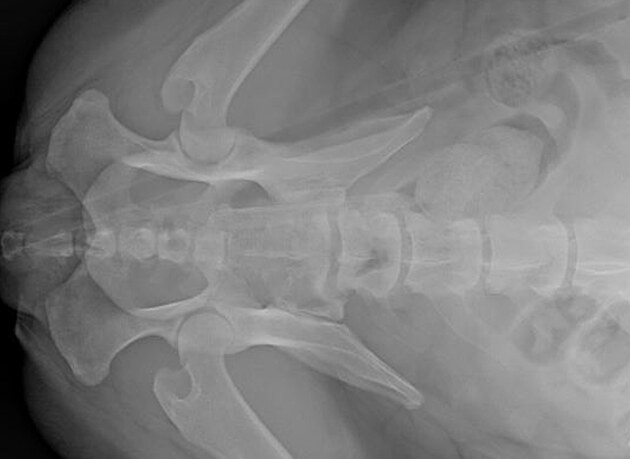

Rentgenový snímek ukazuje, jak šíp pronikl do těla.